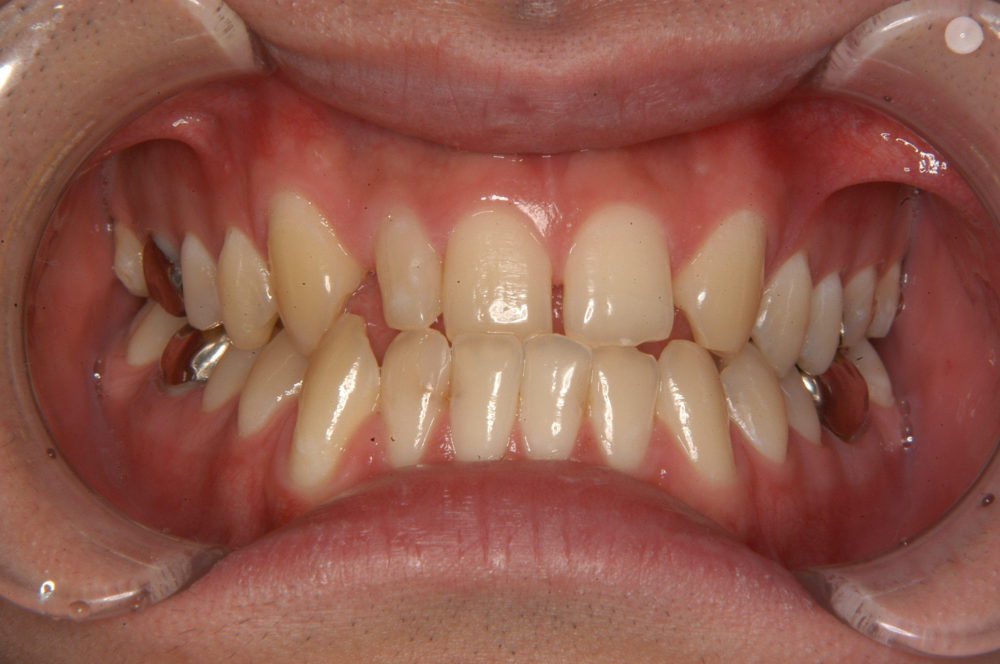

上顎前歯の審美修復のための部分矯正

上顎の右側2番目の歯が矮小歯と呼ばれる小さな歯が審美的にも機能的にも改善が必要な状態です。また、左側は2番目の歯が欠損している状態です。これらを改善するためには右側2番目の歯の形をセラミッククラウンで修復し、左側には欠損した2番目の歯を作る必要があります。修復治療が可能にするために、部分矯正を行いました。

Before

After

前歯に金具を装着後、2番目の歯に修復を施すために歯を移動させてスペースを作る方針を立案しました。

上顎前歯に金具を装着し、約8ヶ月で装置を外し、仮歯にて修復し経過を観察します。歯列の安定を確認した後に最終的な修復物(セラミッククラウンなど)を装着します。

主訴

上顎前歯の審美改善

診断名

空隙歯列

年齢

30歳

装置名

マルチブラケット

非抜歯

治療期間

8ケ月

総額

約20万円